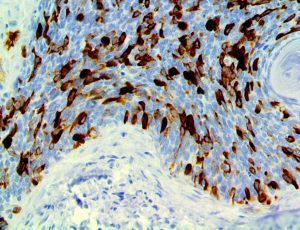

The first cytokines released are interleukin 1β (IL-1β) and tumor necrosis factor-α (TNF-α), which attract a variety of circulating white blood cells (WBCs) to the infection site, including neutrophils, monocytes, macrophages, and natural killer (NK) cells. This response, along with the antipathogenic chemicals released by these cells (i.e., complement), comprise the innate immune response. These cells directly attack the invading pathogen and also release additional cytokines, chief among them interleukin-1 and 6 (IL-6). IL-6 is essential for invoking the adaptive immune response, which calls T-cells, B-cells, and T helper (Th) cells to the infection site. IL-6 also stimulates further recruitment, proliferation and activation of macrophages.

It is the ICU physician who is most likely to witness one of the deadliest manifestations of the abnormal immunological response, the cytokine storm syndrome (CSS). This response is also referred to by some as the cytokine release syndrome (CRS). CSS is characterized by continuous activation and expansion of macrophage and lymphocyte populations, which secrete large amounts of cytokines, causing the cytokine storm. This massive cytokine release is akin to hemophagocytic lymphohistiocytosis (HLH) disease, a syndrome characterized by initial unchecked and persistent activation of cytotoxic T lymphocytes and NK cells.